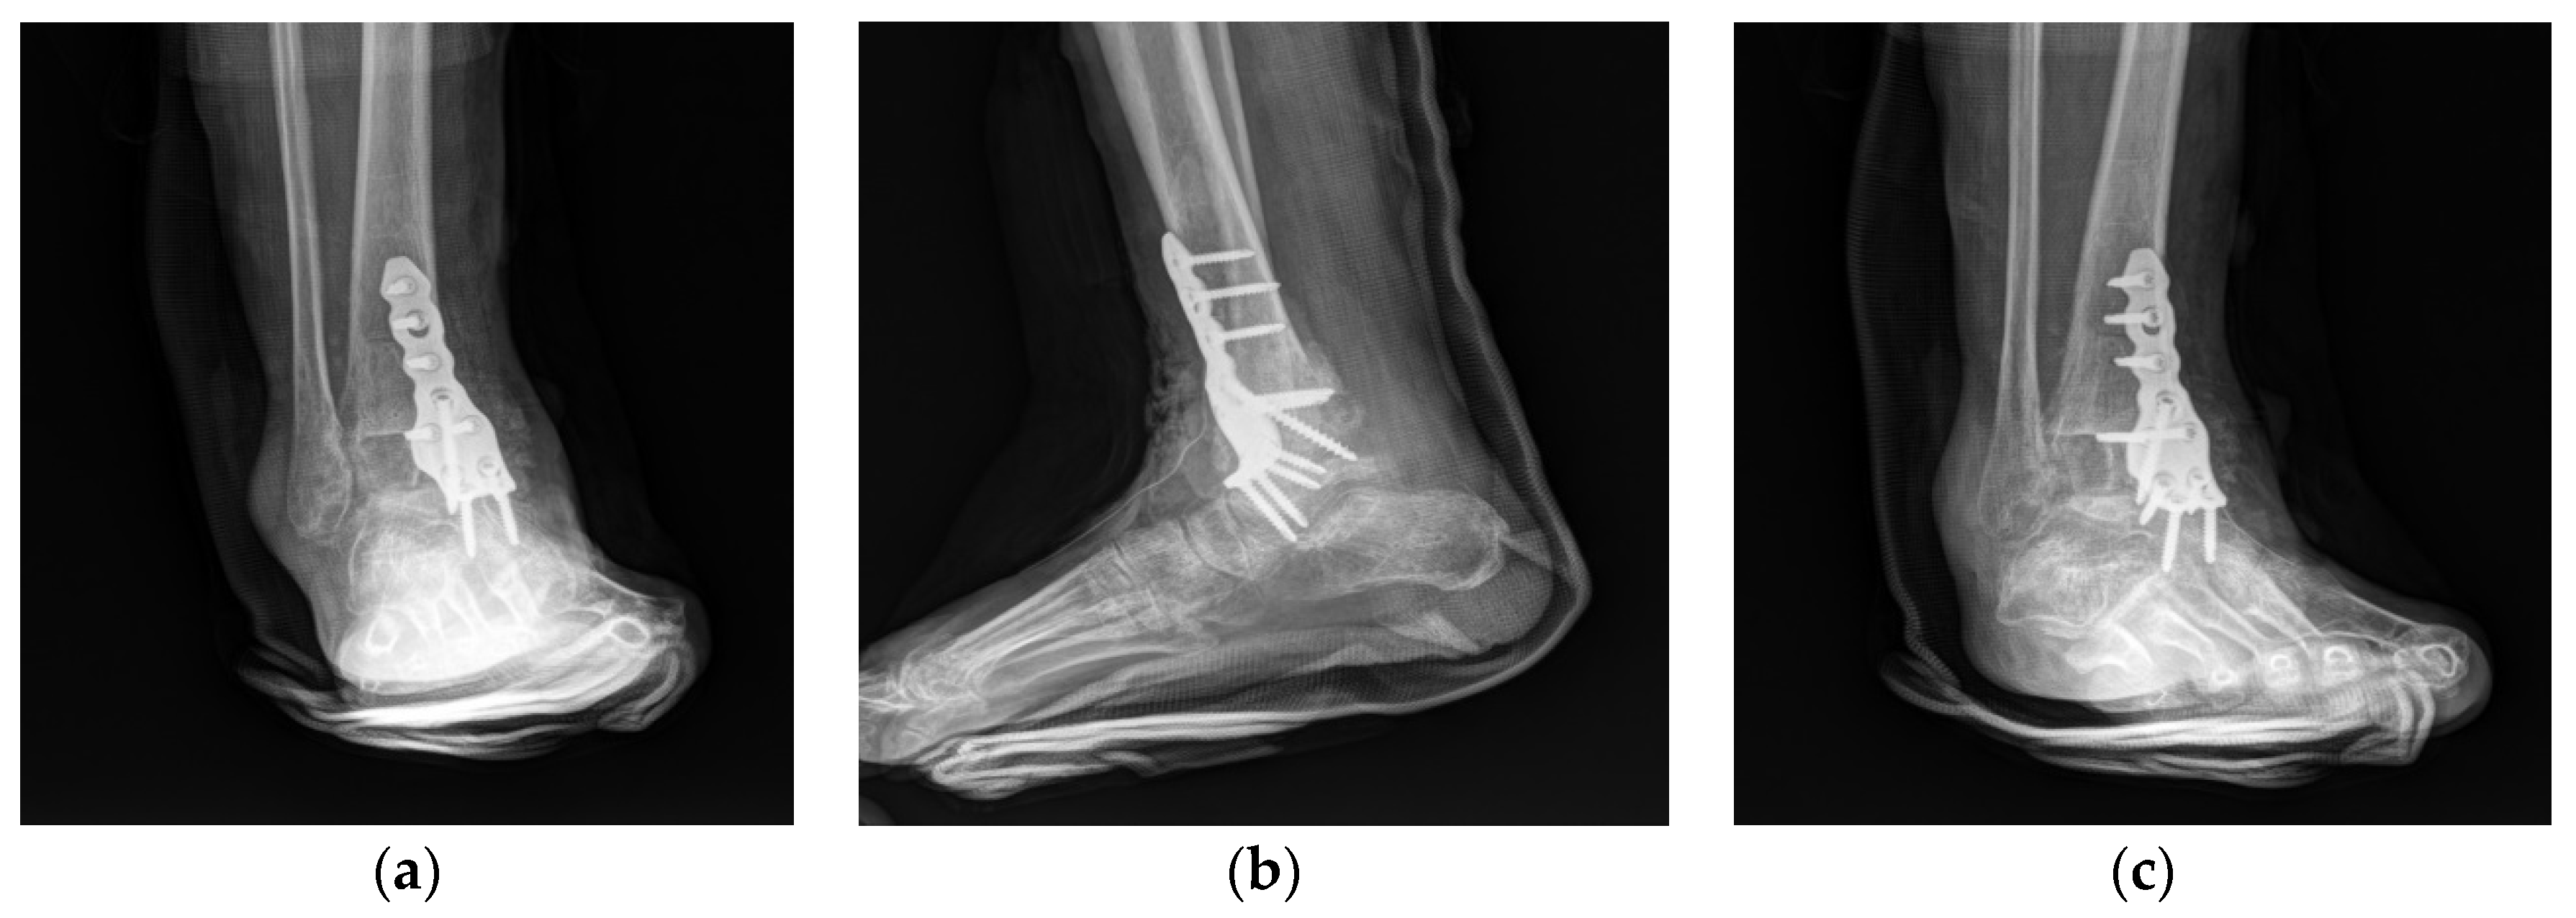

2. Case Presentation